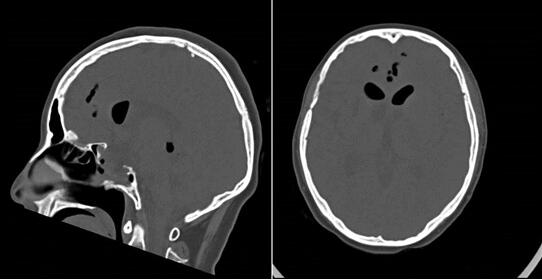

术前CT可见鞍底骨质缺损,颅内积气

三博神经内镜中心任铭主任了解病情后,判断患者很可能是迟发性脑脊液鼻漏,鼻漏逆行感染引发了颅内感染。王女士入院后化验提示脑脊液白细胞升高,蛋白增高,葡萄糖和氯化物降低,头颅CT可见鞍底骨质缺损,颅内积气,核磁显示右侧枕角少量积脓。检查结果证实了任铭主任的判断,患者脑膜炎、颅内感染,导致意识障碍。而发生颅内感染的原因就跟脑脊液鼻漏有关,鼻腔的病菌和外界的气体经漏口进入了颅内。